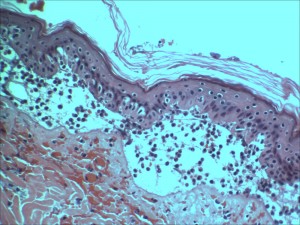

- Histopathology and photomicroscopy